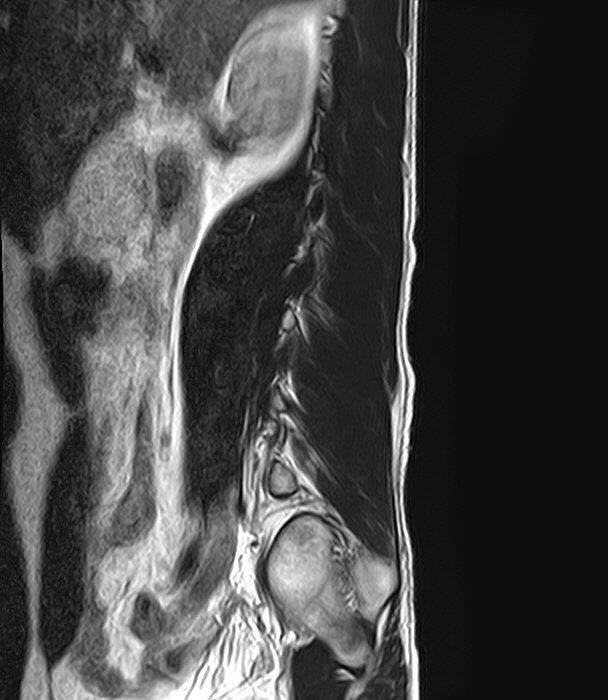

선생님 요추 Mri 판독부탁드립니다 ㅠㅠ

예전 진료에서 척추전방전위증과 그로인한 퇴행성 디스크 그리고 팽윤이 있다고 들었습니다.

현재 제가 디스크가 터진곳이 있을까요?

집근처 병원을 세곳을다니는중인데 어떤곳은 디스크는 멀쩡하다 퇴행성만있을뿐.

어떤곳은 디스크가 터졌다고 하는게 어떤곳이 맞는건가요?

혹시 디스크가 터진게 없다면 통증이 생기는이유는 단순히 척추전방증으로인한 퇴행성디스크와 팽윤 때문인건가요?

디스크가 명확하게 튀어나와 신경뿌리를 압박하는 병변은 보이지 않는 MRI로 생각됩니다.